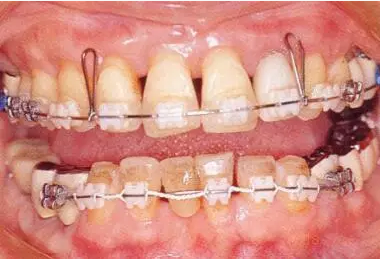

2222222222.png

40歲,女性。來院主訴為牙齦出血,牙體晃動?;颊卟晃鼰?,因此沒有全身性問題。有明顯的牙周炎,發(fā)生了牙體移動,前牙區(qū)前突。下頜右側(cè)磨牙缺失,醫(yī)生認為有必要進行包括牙周修復(fù)、正畸治療、種植治療等在內(nèi)的綜合性治療。

22222222222222.png

▲圖19-2,3

上下頜咬合面照。